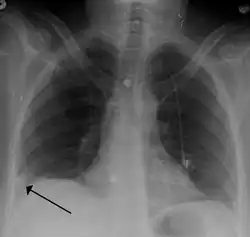

- Chest X-rays are often done on people with shortness of breath to help rule out other causes, such as congestive heart failure and rib fracture. Chest X-rays in PE are rarely normal,[70] but usually lack signs that suggest the diagnosis of PE (for example, Westermark sign, Hampton's hump).

Pulmonary embolism (white arrow) that has been long-standing and has caused a lung infarction (black arrow) seen as a reverse halo sign